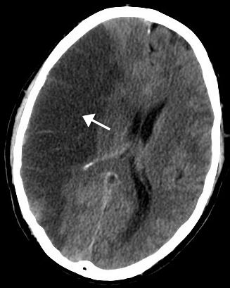

CT scan slice of the brain showing a right-hemispheric ischemic stroke. (Courtesy Wikipedia.)